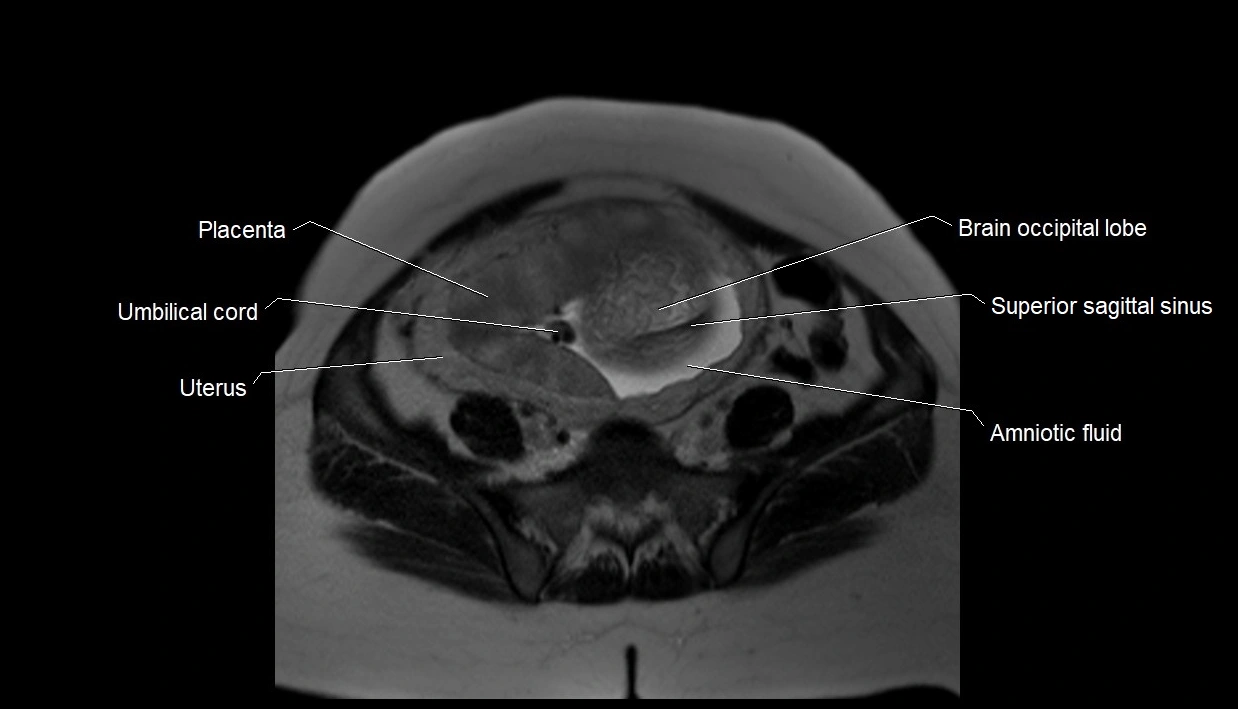

MRI Appearance

T2 HASTE (T2 GRE):

• Amniotic fluid shows very bright hyperintense signal

• Provides natural contrast against fetus and placenta

• Small particles (vernix) may appear as scattered hypointense foci within bright fluid

MRI image

image